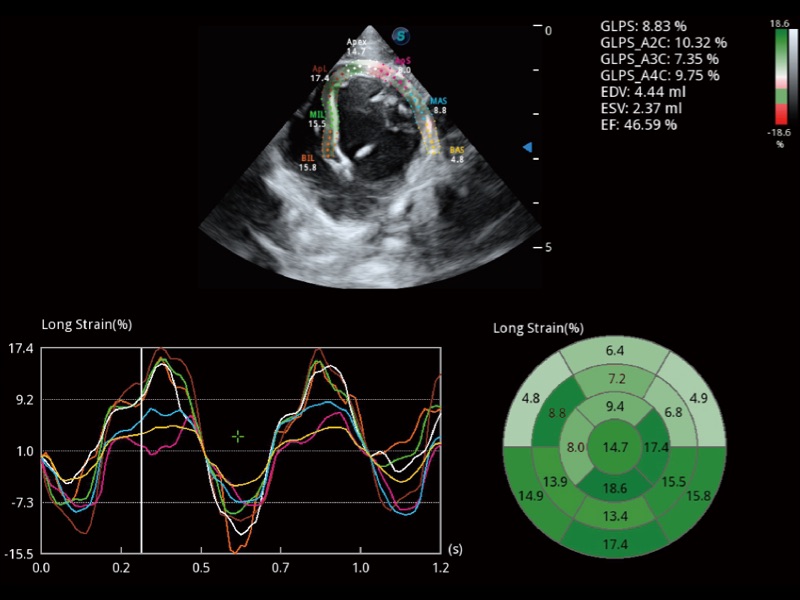

(犬)四腔心MQA

• Auto EF 心内膜自动描迹

能够基于左心室壁追踪和辛普森法,自动计算射血分数,支持多个可移动点描迹,与手动测量相比,极大节省了动物医生的时间和精力。